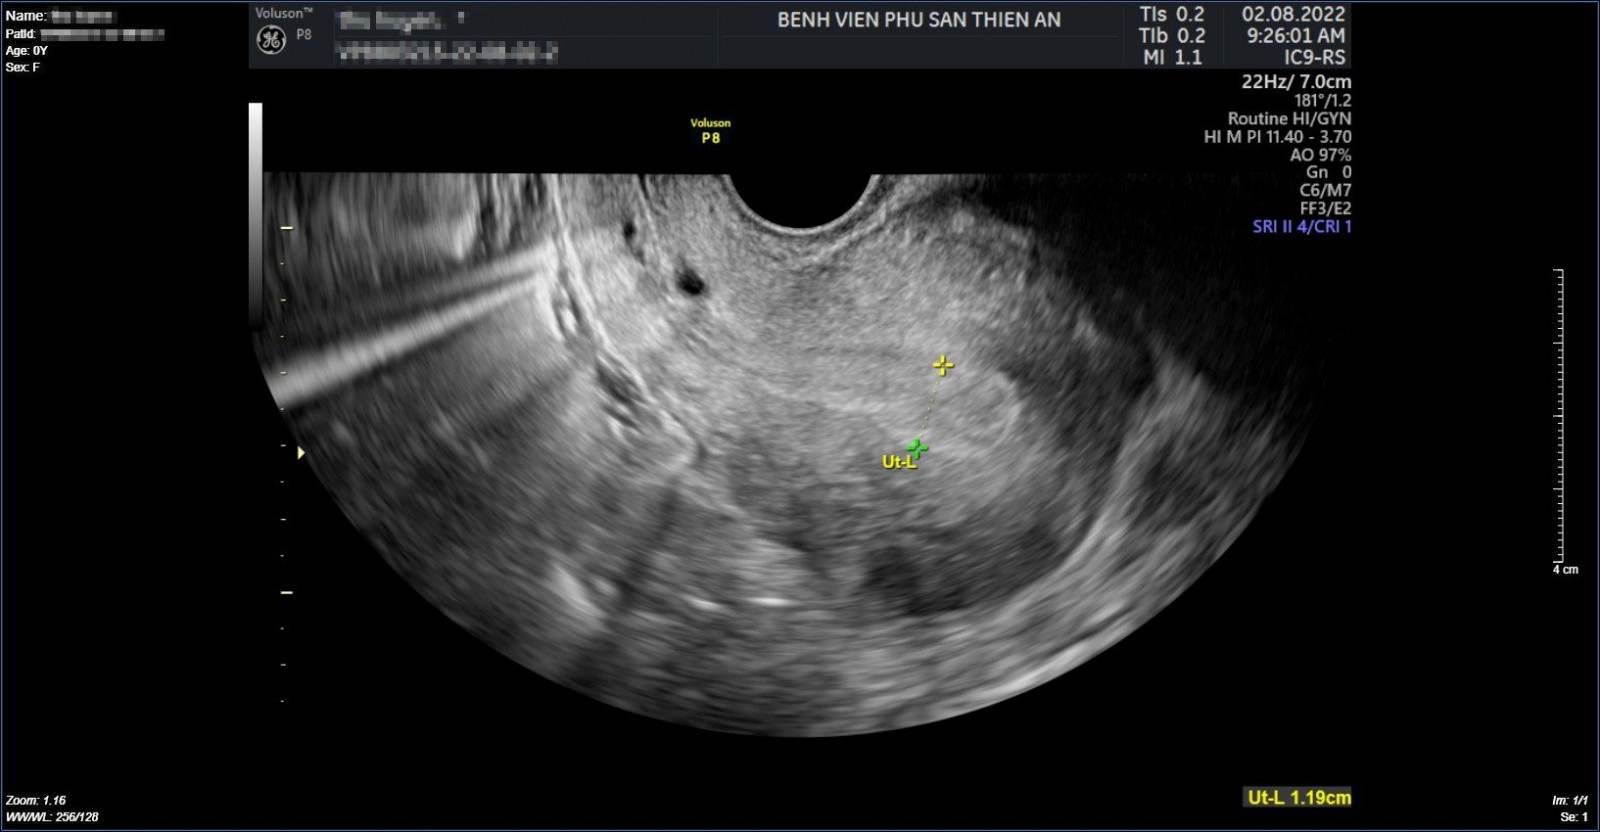

Hình ảnh tử cung của chị H. sau khi đã phẫu thuật bóc tách u xơ tử cung

Tại Bệnh viện Phụ sản Thiện An, ca phẫu thuật nội soi đã được thực hiện bởi GS Nguyễn Viết Tiến đã bóc tách khối u thành công, xử lý hoàn toàn các bệnh lý phụ khoa và sẵn sàng cho hành trình làm mẹ. Sau ca mổ, chị hồi phục sức khỏe nhanh chóng, ít đau đớn và cảm nhận được sự hồi phục nhanh chóng của cơ thể do không còn chướng bụng, đau vùng hạ vị.